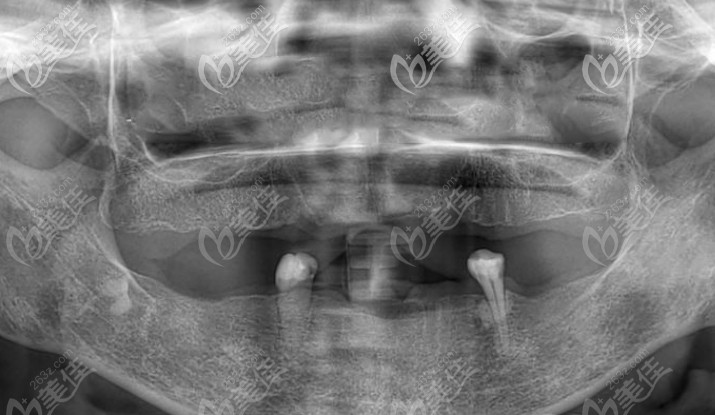

▲以上這是張奶奶拍的全景片,根本無法咀嚼食物

經(jīng)過咨詢醫(yī)生才得知是由于長期缺牙導(dǎo)致牙槽骨吸收萎縮,通過一系列的拍片檢查,建議張奶奶拔掉剩余無用牙齒,做滿口bps吸附性義齒,來恢復(fù)她的咀嚼功能。